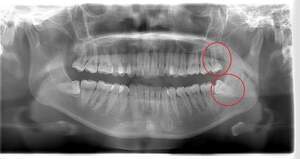

右下の親知らずが疼く症例

- 抜歯前写真(レントゲン)

| 年齢 | 30代・女性 |

|---|---|

| 主訴 | 右下親知らずが疼く |

| 親知らずの生え方 | 横向きに生えている |

| 抜歯時間 | 40分 |

| 費用 | 約8,000円(保険診療、CT代含む) |

| 抜歯内容 | 右下の親知らずは横向きに生えて埋まっているため、麻酔をし親知らずの奥に切開を入れて歯ぐきを開き、歯を囲んでいる骨を削り歯の頭部分を割って出してから、残った根の部分を取り出して抜歯は終了しました。 歯ぐきを切った部分は糸で縫っています。このケースでは根の先端が神経に近く麻痺のリスクがありましたが事前にCTを撮影し、神経との位置関係を確認していたため、麻痺が残ることはありませんでした。 約1週間後に糸取りを行い、その際も多少の痛みや腫れはありましたが後日その痛みも無くなりました。 |